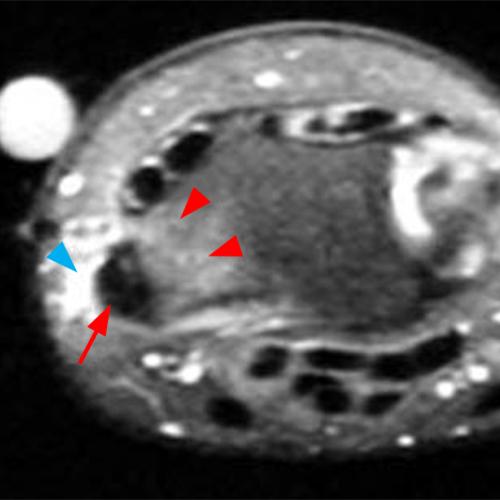

Radiography: Radiographs are not the primary imaging modality for diagnosing DQT, but they can suggest chronic inflammation in the first dorsal compartment by revealing focal cortical erosion, sclerosis, or periosteal bone apposition of the radial styloid sheath, along with overlying soft tissue swelling (Figure 6).28 These findings, though nonspecific, may support a clinical diagnosis of DQT. However, the absence of these findings on radiographs does not rule out the condition.

Figure 6: A 53-year-old female with radial-sided wrist pain for 4 months. A postero-anterior wrist radiograph demonstrates plain film changes of de Quervain's tenosynovitis. The radial styloid demonstrates subtle periosteal bony apposition (arrowhead), and adjacent soft tissue swelling is evident (arrow). Axial fat-suppressed proton-density image from the same patient demonstrates peritendinous edema (blue arrowhead), mild tendon enlargement (arrow), and reactive marrow edema of the radius (red arrowheads).